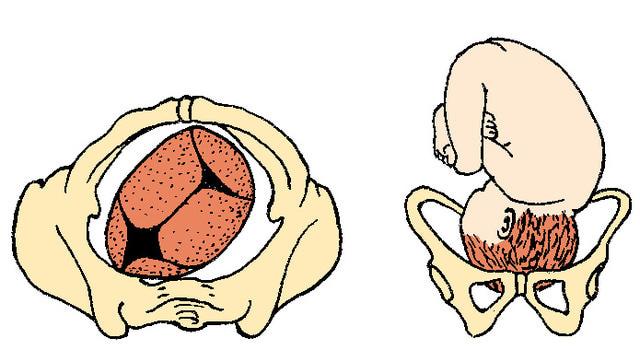

Footling Breech

What is the incidence of abnormalities in breech babies?

6.3%

What is the incidence of abnormalities in vertex babies?

2.4%